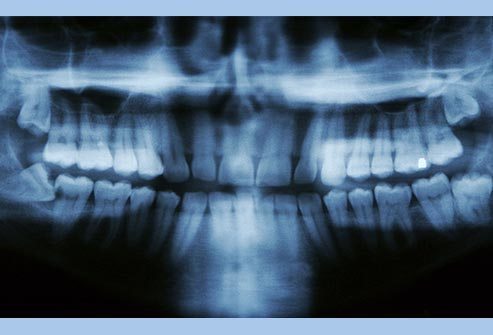

Problemet me dhëmbët e pjekurisë.

Nëse dentisti juaj thotë se dhëmbët tuaj të pjekurisë, ose molarët e tretë po dalin pa probleme, konsideroni veten me fat. Shumica e njerëzve – diku 90% – kanë të paktën një dhëmb të pjekurisë që është i ndikuar apo jo në gjendje të rritet plotësisht. Problemet me dhëmbët e pjekurisë mund të shkaktojnë prishjen e dhëmbëve, dëmtimin e dhëmbëve fqinjë si dhe sëmundje të mishit të dhëmbëve. Dhëmbët e pjekurisë përgjithësisht dalin në mes të moshës 17 dhe 25. Dentisti juaj duhet te ndjekë progresin e tyre. Nëse ju shkaktojnë ndonjë problem, ju sigurisht do të keni nevojë t’i largoni.